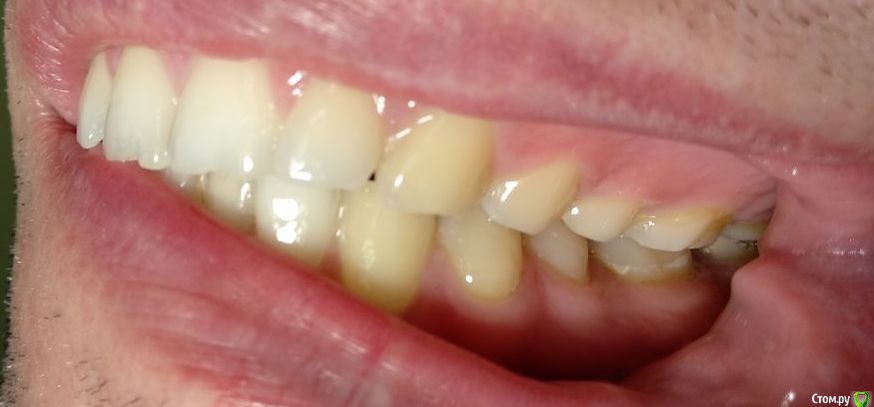

Здравствуйте! Откололся кусок зуба. 8 октября сделали КЛКТ (3Д снимок всех зубов). Вскрыли зуб, была проведена девитализация. Поставили диагноз: хронический фиброзный пульпит 37 зуба. 18 октября было проведено первичное лечение 3-х канального зуба эндомотором с использованием микроскопа и системы коффердам. Все каналы были запломбированы гуттаперчивыми штифтами на силлере методом латеральной конденсации Adseal, внутрь заложена ватка и поставлена временная пломба дентин-паста. 29 октября ортопед №1 посмотрел прицельный снимок (см. снимок зуба 2) и сам зуб, пломбу не снимал. Озвучил, что у меня низкая высота зуба, мне нужно установить культевую кобальт-хромовую вкладку и сверху покрыть металлокерамической коронкой зуб. Также сказал, что циркониевая вкладка мне не подходит из-за высоты. Однако, поскольку ортопед №1 уходил на обучение, мне было предложено обратиться в другую клинику к другому ортопеду. 1 ноября ортопед №2 посмотрев мой зуб без снимка заявил, что у меня сохранились три стенки у зуба и мне надо просто закрыть пломбой этой зуб. Поскольку ортопед №2 предложил диаметрально противоположное лечение зуба, то я решил обратиться в третью клинику. Ортопед №3 посмотрев снимок моего зуба, сам зуб, в том числе внутри (снял мою временную пломбу из дентина), заявил, что у меня низкая высота зуба и мне нельзя ставить культевую вкладку и коронку. И было предложено сделать вкладку из пресс керамики overlay. Также когда удалили временную пломбу у меня увидели кариес на этом зубе. В конце приема мне взамен снятой пломбы установили временную пломбу парасепт.

Сделал несколько фотографий, тк не совсем понял с какого ракурса делать фото с сомкнутыми зубами.